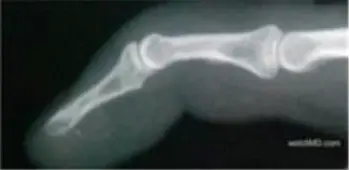

• Mallet finger 為手指遠端指節 (DIP joint) 無法主動伸直,呈下垂狀。

• 主要病因是在基節端或末節底部的 terminal extensor tendon(終端伸肌腱)斷裂或撕脫,偶伴小片骨性撕脫。